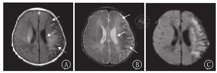

患儿均行头颅MRI+DWI检查,未行磁共振血管成像(MRA)检查。头颅MRI显示缺血性脑梗死病灶部位为多发斑片状或不规则大片状异常信号,呈长T1及长T2信号,DWI均呈高信号(图1),出血表现为短T1信号,位于梗死区内。7例为出血性脑梗死(17.90%),32例为缺血性脑梗死(82.10%)。

MRI检查是NCI的金标准[10]。常规MRI多在发病后5~7 d表现出T1WI及T2WI信号异常,而DWI可在NCI发病后6 h即可发现异常,表现为DWI高信号[11]。本研究中,患儿DWI均显示病灶部位高信号改变,累及大脑中动脉,以左侧为主,与文献[3]报道一致。